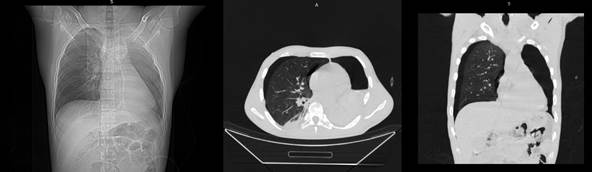

а б в

Рисунок 1. МСКТ.

Тяжелая ТОГК. Мультипланарная 3D-реконструкция: поперечный перелом 6, 7, 8, 9, 10 –х ребер слева по лопаточной линии, поперечный перелом тел 8, 9, 10 ребер слева по средней подмышечной линии (а), аксиальный и фронтальные срезы: ушиб обоих легких, двухсторонний пневмоторакс, двухсторонний гемоторакс, подкожная эмфизема переднезаднебоковой поверхности грудной клетки с двух сторон (а, б).